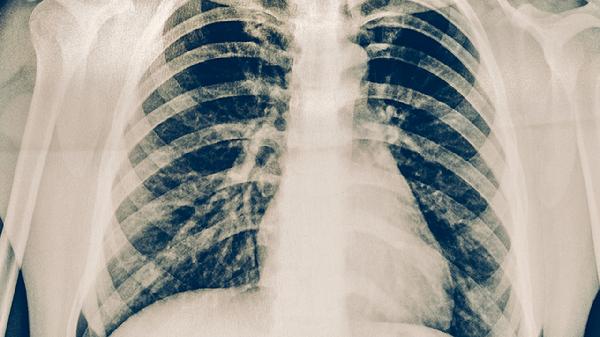

放射性肺炎可通过中药调理辅助治疗,常用药物包括百合固金口服液、养阴清肺糖浆、黄芪颗粒、生脉饮、清肺消炎丸等。放射性肺炎通常由放射线损伤肺组织导致,可能伴随咳嗽、气短、胸痛等症状。建议在医生指导下规范使用中药,并配合氧疗等西医治疗。

放射性肺炎患者除中药治疗外,日常需保持居住环境空气流通,避免油烟刺激。饮食宜选择银耳、雪梨等润肺食材,限制辛辣食物摄入。适当进行呼吸训练如腹式呼吸,但避免剧烈运动加重缺氧症状。定期复查胸部CT观察肺纤维化进展,若出现发热或呼吸困难加重应及时复诊调整治疗方案。